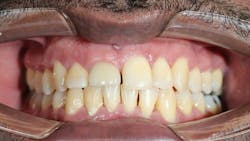

- Labialization of the dental implant, especially in the maxillary anterior region (figure 1)